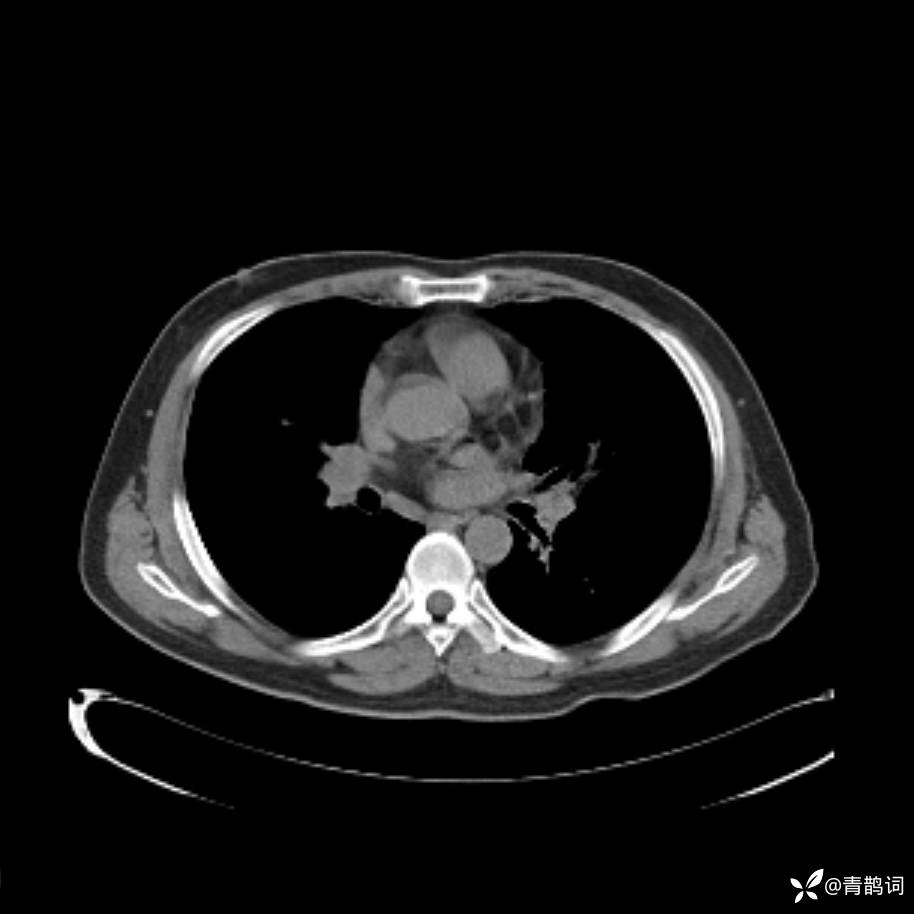

患者年龄:30岁。

患者性别:男。

简要病史:左颜面部肿胀2年,反复咳嗽咳痰,逐渐加重。

辅助检查

结合病史及影像学表现,期待评论区各位老师各抒己见~